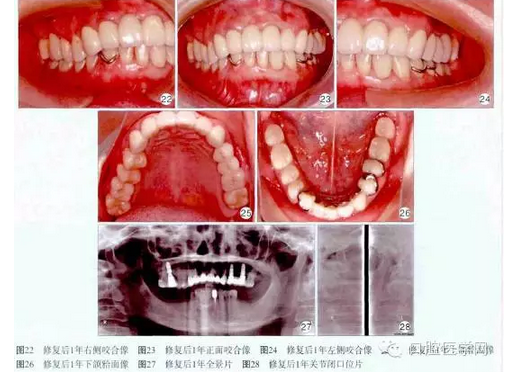

1個月后用Fuji玻璃離子水門汀(GC公司,曰本)永久粘固上頜烤瓷冠撟。修復后1年復查,患者訴義齒咀嚼、發(fā)音功能良好,舒適美觀,無壓痛。檢查:口腔衛(wèi)生良好,牙齦正常,種植體穩(wěn)固,咬合良好(圖22~26)。X線片示:16、24、26種植體頸部無明顯骨吸收,顳下頜關節(jié)維持原有狀態(tài)(圖27~28)。